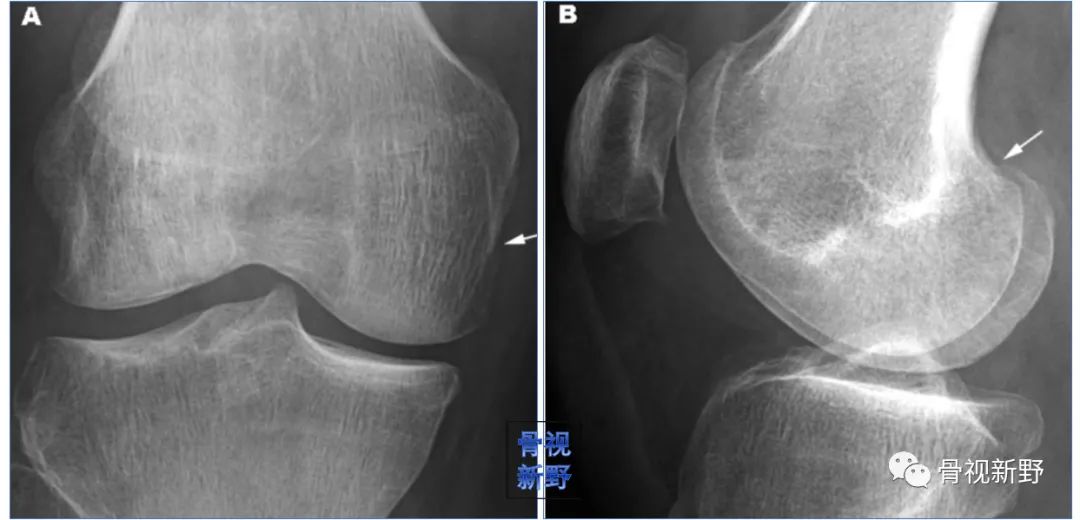

影像诊断:部分Hoffa骨折X线片不能提供明确的诊断,漏诊率较高。需要CT或MRI检查,并根据患者的病史、查体及影像学检查予以确诊。

部分Hoffa骨折普通X光片易漏诊

CT扫描在矢状位、轴位容易发现骨折及骨折线的走形方向